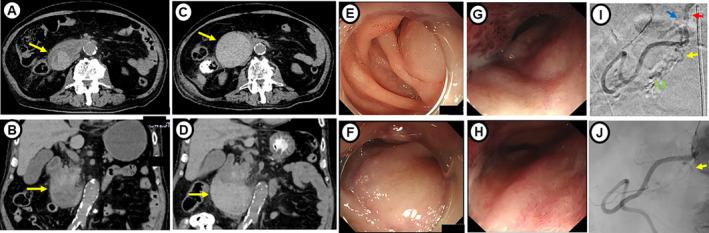

A 79-year-old man undergoing treatment with warfarin for atrial fibrillation and hemodialysis for renal failure was transferred to our hospital for rehabilitation. During a maintenance hemodialysis session, blood pressure was shown to be elevated and an intramural duodenal hematoma suddenly occurred. After 3 days, the hematoma had enlarged and angiographic embolization was performed, with complete resolution noted after 2 months. Occurrence of an intramural duodenal hematoma during hemodialysis is rare. However, acute abdominal pain with symptoms indicating obstruction in patients undergoing such treatment should raise suspicion regarding an intramural duodenal hematoma. Although conservative treatment is often effective for a nontraumatic intramural hematoma, early angiographic embolization is preferred when disruption of anticoagulant therapy is difficult or for patients with failed medical treatment.

一名79岁男性,因心房颤动接受华法林治疗,因肾衰竭接受血液透析,被转至我院进行康复治疗。在一次维持性血液透析过程中,血压升高,突然发生十二指肠壁内血肿。3天后,血肿增大,遂行血管造影栓塞术,2个月后血肿完全消退。血液透析期间发生十二指肠壁内血肿的情况较为罕见。然而,接受此类治疗的患者出现急性腹痛并伴有梗阻症状时,应怀疑十二指肠壁内血肿。对于非创伤性壁内血肿,保守治疗通常有效,但在抗凝治疗中断困难或药物治疗无效的患者中,早期血管造影栓塞术更为可取。